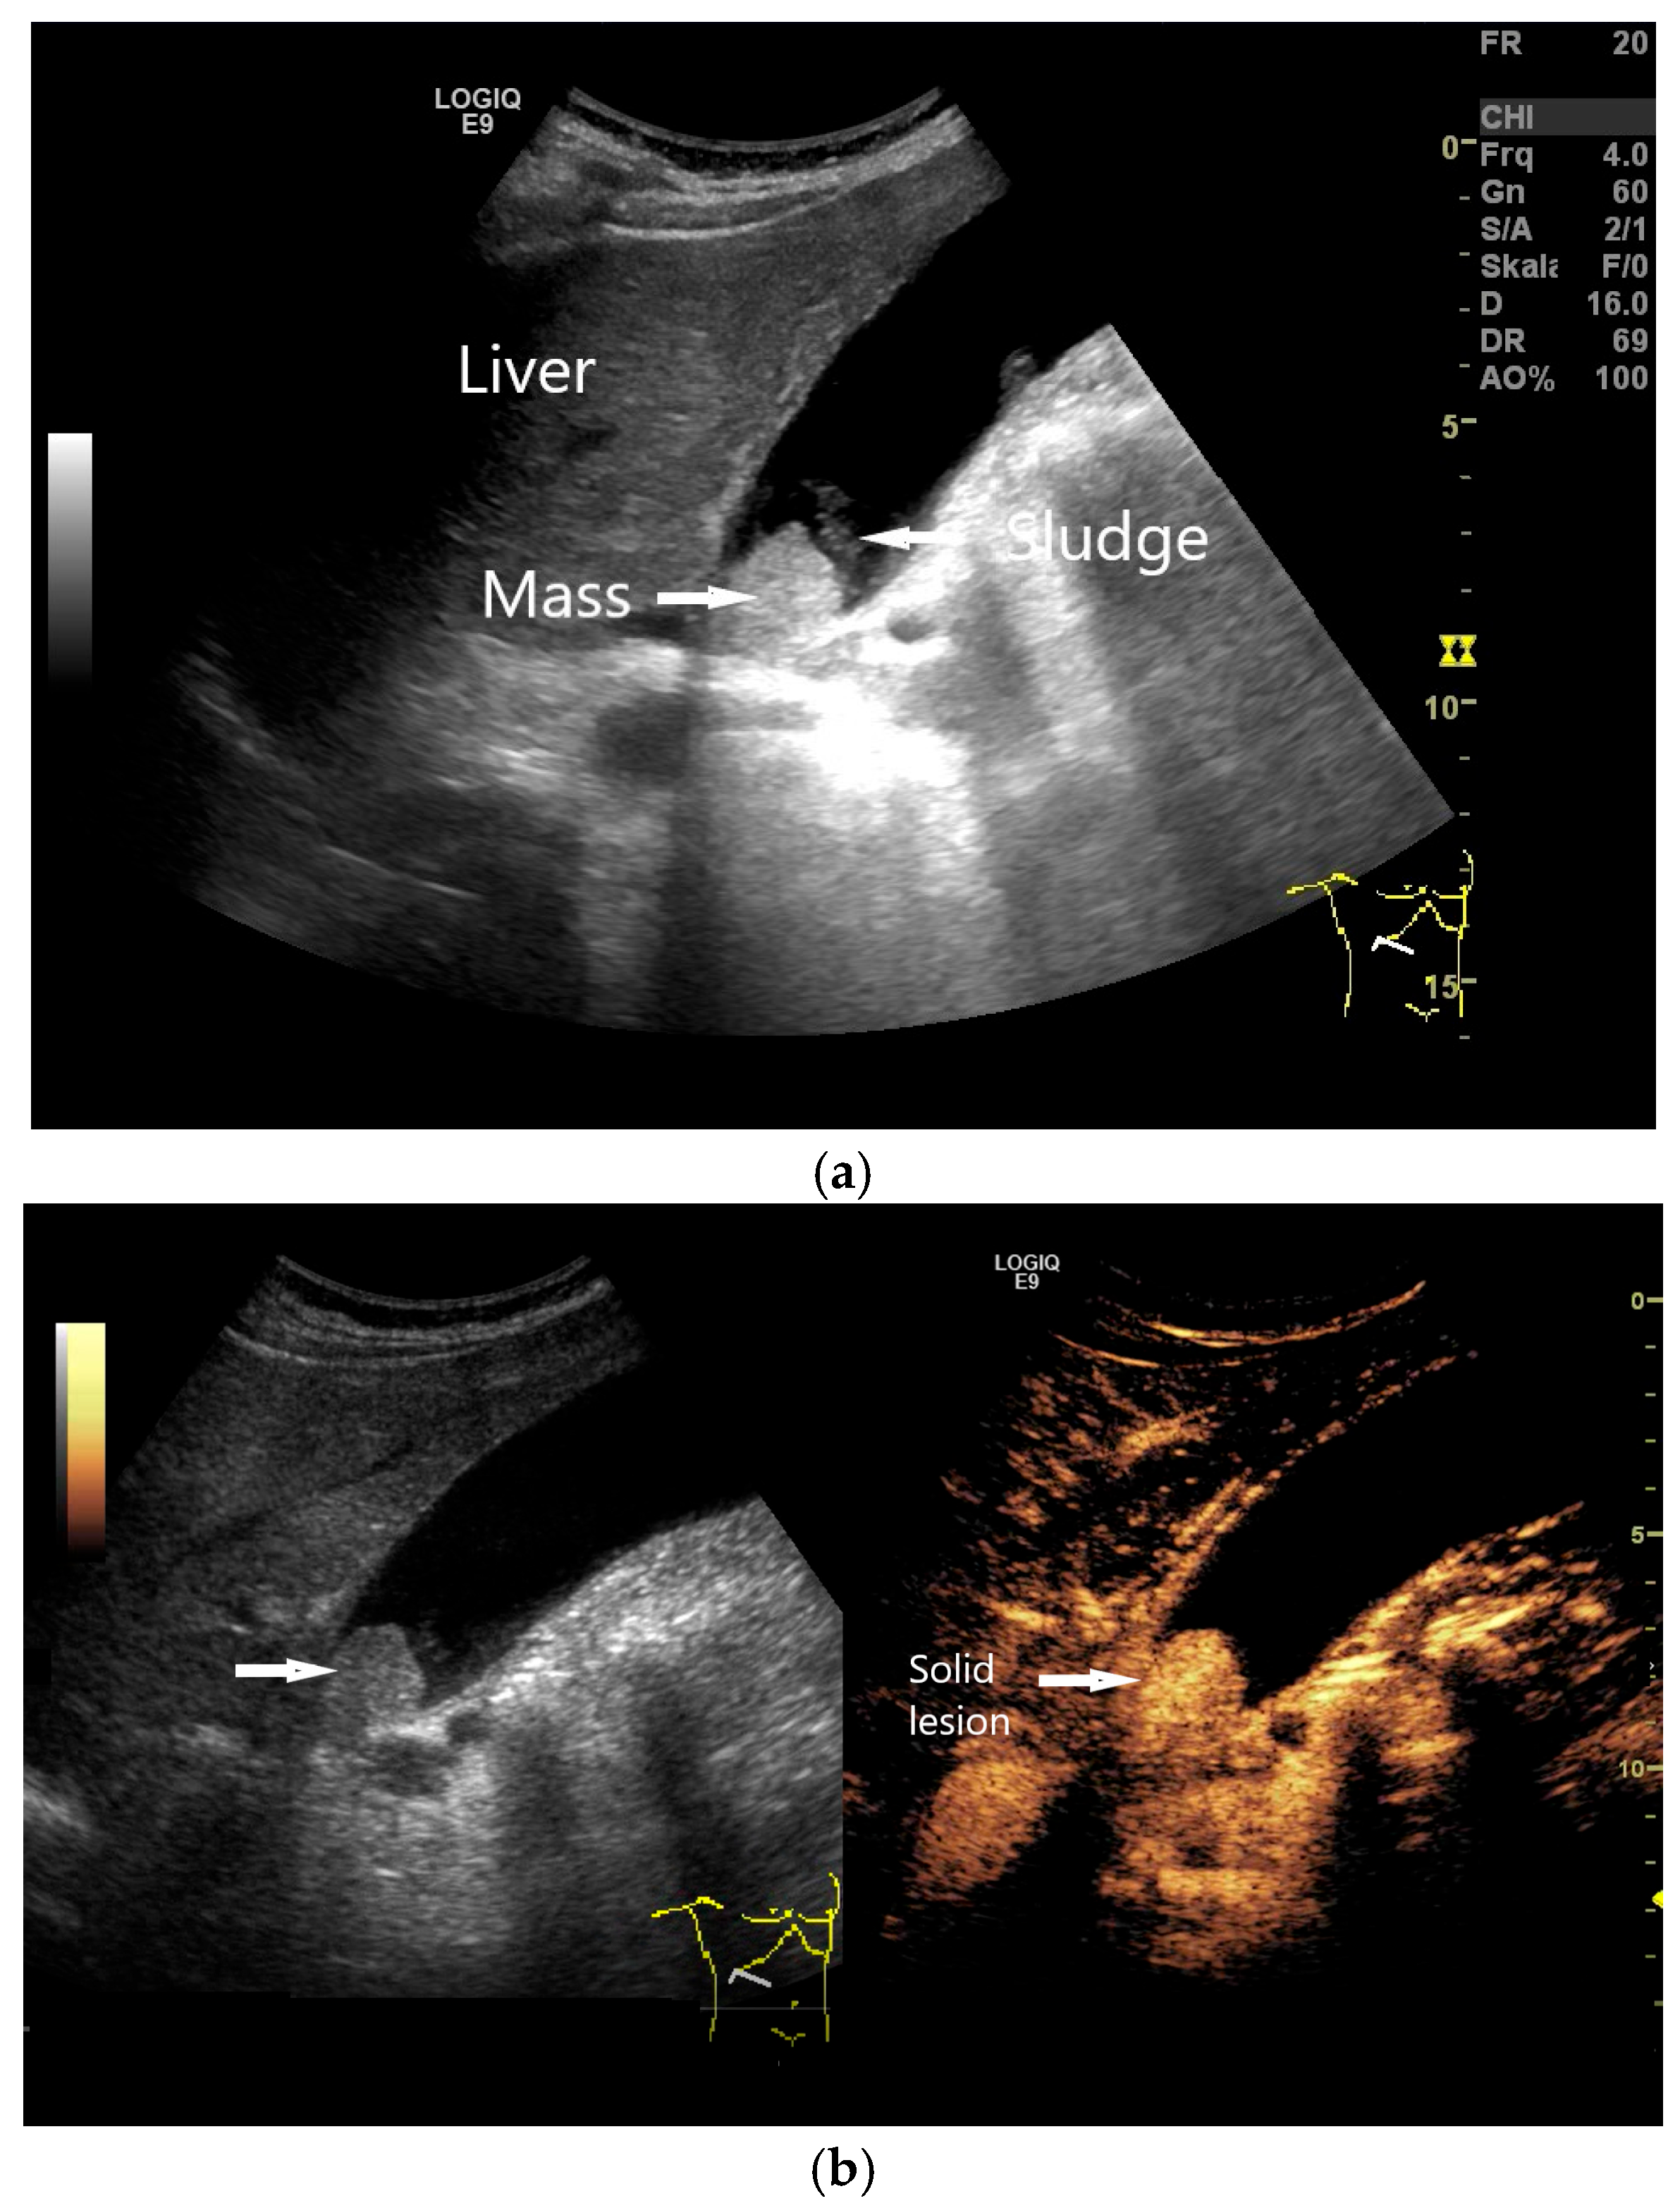

4.2. Focal Gallbladder Wall Thickening

- Verma, A.; Kumar, I.; Yadav, Y.; Kumar, S.; Puneet; Shukla, R.C.; Verma, A. Utility of contrast-enhanced ultrasound in differentiation between benign mural lesions and adenocarcinoma of gallbladder. J. Med. Ultrasound 2020, 28, 143–150. [Google Scholar] [CrossRef]

- Dong, Y.; Xu, B.; Cao, Q.; Zhang, Q.; Qiu, Y.; Yang, D.; Yu, L.; Wang, W.-P. Incidentally detected focal fundal gallbladder wall thickening: Differentiation contrast enhanced ultrasound features with high-resolution linear transducers. Clin. Hemorheol. Microcirc. 2020, 74, 315–325. [Google Scholar] [CrossRef]